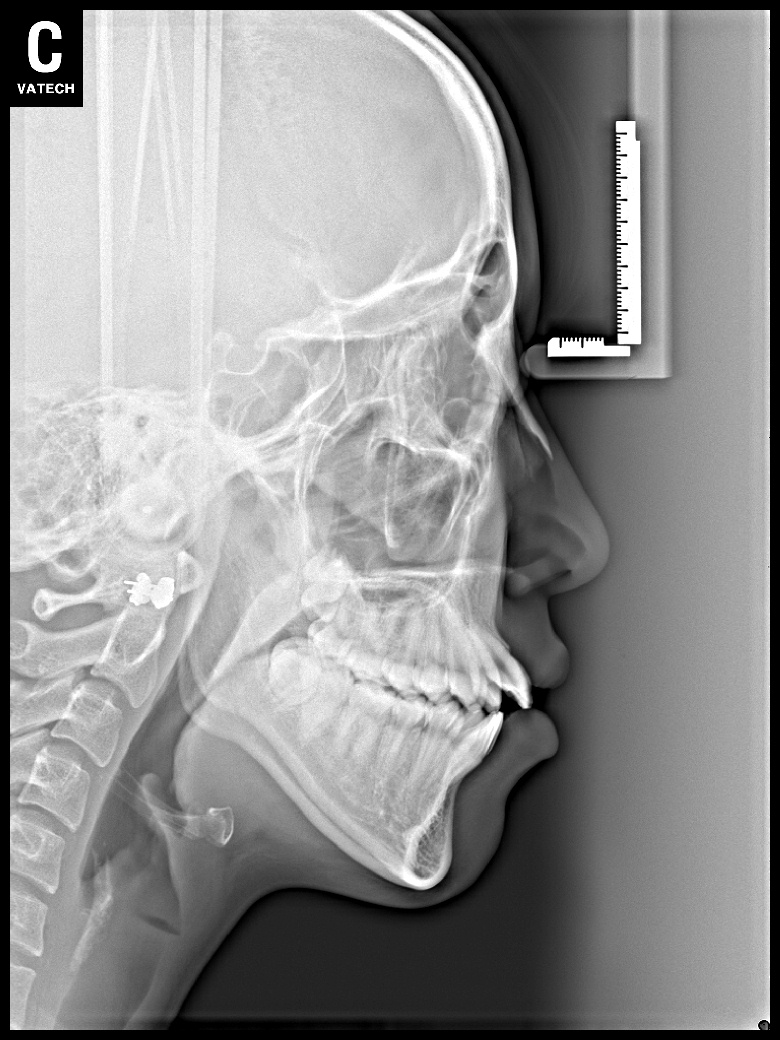

치료 후 사진입니다.